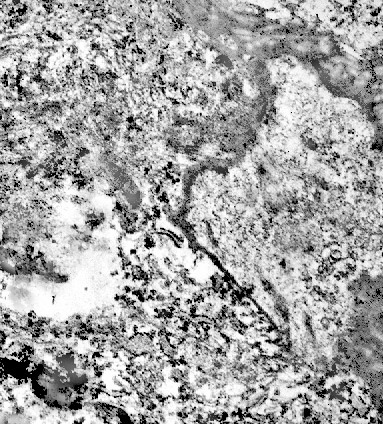

Fig.15